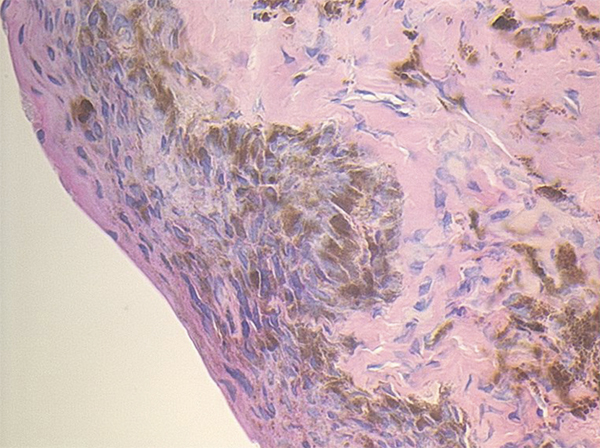

Fig. 11-20 Prolifération mélanocytaire intra-épithéliale avec atypies modérées.

Noter l’aspect partiellement désorganisé des couches basales et parabasales de l’épithélium. Au niveau des assises plus superficielles, l’architecture du corps muqueux de Malpighi est respectée et on n’observe pas d’aspect d’ascension d’éléments mélanocytaires.